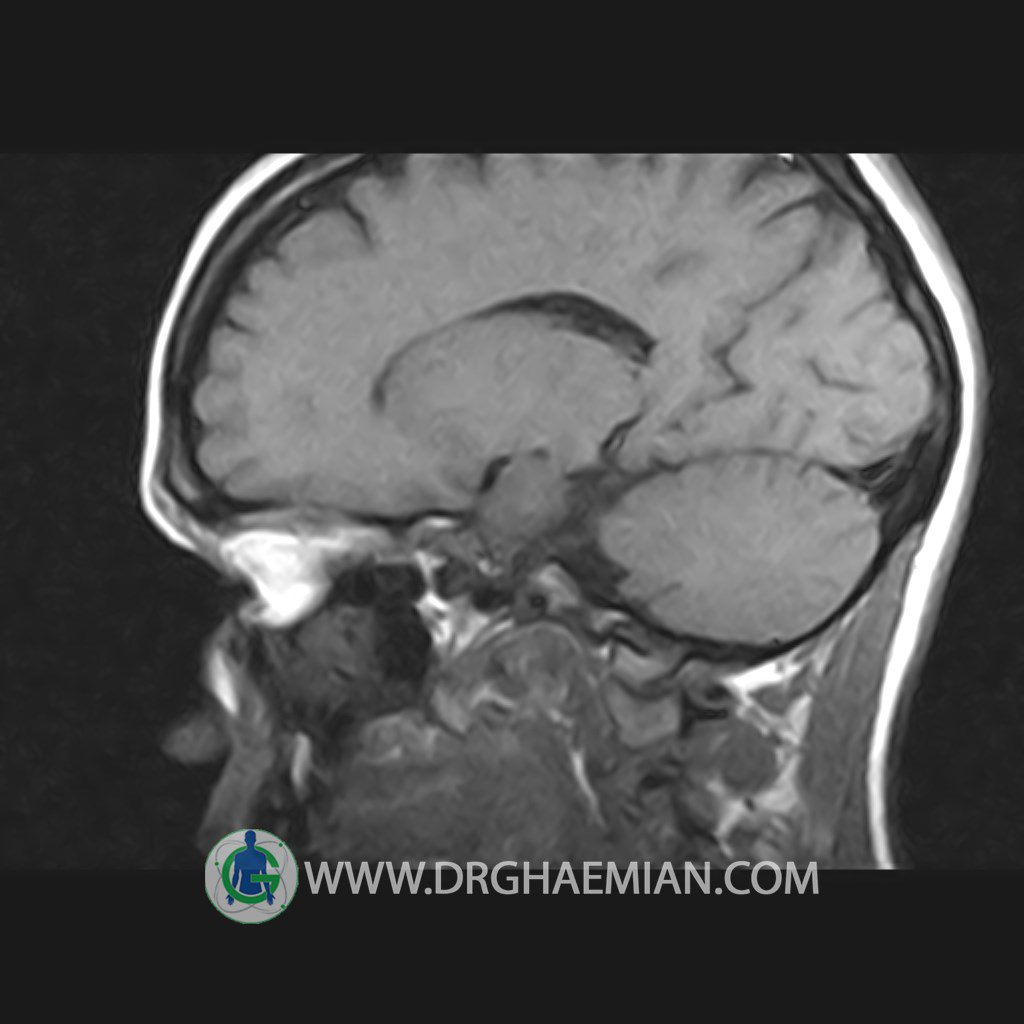

پزشکان اغلب از تصویربرداری ام آر آی برای تشخیص و درمان عارضه های پزشکی که فقط با استفاده از اشعه ایکس یا میدان مغناطیسی و امواج رادیویی قابل مشاهده است، استفاده می کنند. دستگاه ام آر آی تصاویر دقیق از ساختار های داخلی بدن ایجاد می کند. در این کیس هیپرپلازی هیپوفیز و آدنوم مشاهده می شود.

HYPOPHYSIS MRI

(with and without contrast)

Technique: Axial , coronal T1 , Axial , coronal , sagittal T2 , Axial, coronal T1 post Gd & 64 dynamic thin coronal slices.

The sella shows normal size , position and configuration .

The borders of its floor and walls are smooth and sharply defined .

The infundibulum is centered and of normal size .

The optic chiasm and suprasellar spaces appear normal .

The cavernous sinus and imaged portions of the internal carotid artery and carotid siphon are unremarkable .

Evaluable portions of the neurocranium show no abnormalities .

The sphenoid sinus is clear and pneumatized .

– Mild convexity at superior border of pituitary gland with post contrast homogeneous enhancement suggestive for pituitary hyperplasia & iso signal adenoma

is seen